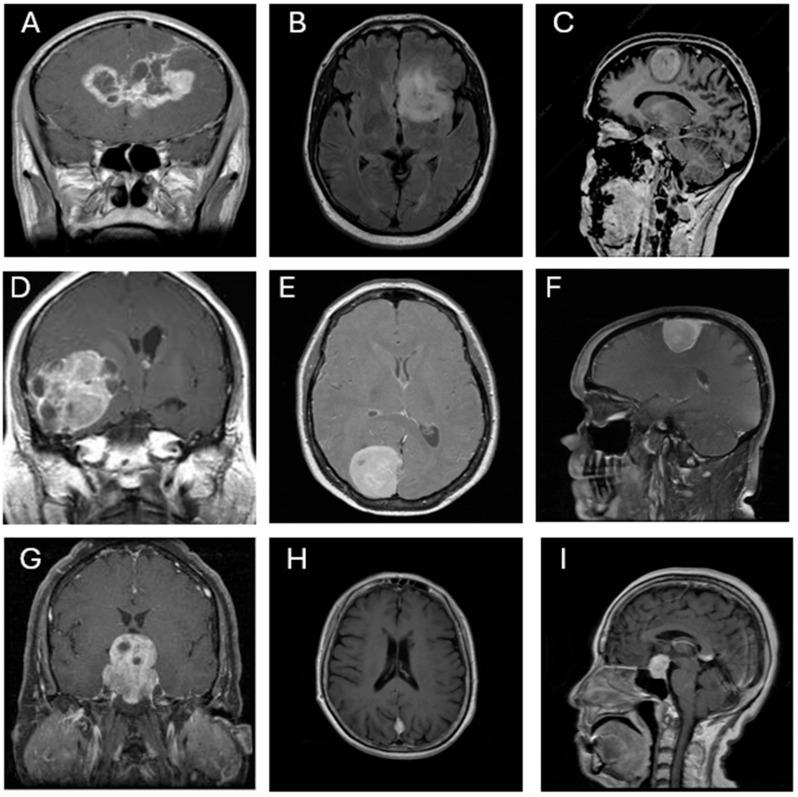

: Accurate classification of brain tumors is critical for treatment planning and prognosis. While deep convolutional neural networks (CNNs) have shown promise in medical imaging, few studies have systematically compared multiple architectures or integrated ensemble strategies to improve diagnostic performance. This study aimed to evaluate various CNN models and optimize classification performance using a majority voting ensemble approach on T1-weighted MRI brain images. : Seven pretrained CNN architectures were fine-tuned to classify four categories: glioblastoma, meningioma, pituitary adenoma, and no tumor. Each model was trained using two optimizers (SGDM and ADAM) and evaluated on a public dataset split into training (70%), validation (10%), and testing (20%) subsets, and further validated on an independent external dataset to assess generalizability. A majority voting ensemble was constructed by aggregating predictions from all 14 trained models. Performance was assessed using accuracy, Kappa coefficient, true positive rate, precision, confusion matrix, and ROC curves. : Among individual models, GoogLeNet and Inception-v3 with ADAM achieved the highest classification accuracy (0.987). However, the ensemble approach outperformed all standalone models, achieving an accuracy of 0.998, a Kappa coefficient of 0.997, and AUC values above 0.997 for all tumor classes. The ensemble demonstrated improved sensitivity, precision, and overall robustness. : The majority voting ensemble of diverse CNN architectures significantly enhanced the performance of MRI-based brain tumor classification, surpassing that of any single model. These findings underscore the value of model diversity and ensemble learning in building reliable AI-driven diagnostic tools for neuro-oncology.

七个预训练的CNN架构被微调以对四类进行分类:胶质母细胞瘤、脑膜瘤、垂体腺瘤和无肿瘤。每个模型使用两种优化器(SGDM和ADAM)进行训练,并在一个公共数据集上进行评估,该数据集被分为训练集(70%)、验证集(10%)和测试集(20%)子集,并在一个独立的外部数据集上进一步验证以评估泛化能力。通过汇总所有14个训练模型的预测构建多数投票集成。使用准确率、Kappa系数、真阳性率、精确率、混淆矩阵和ROC曲线评估性能。